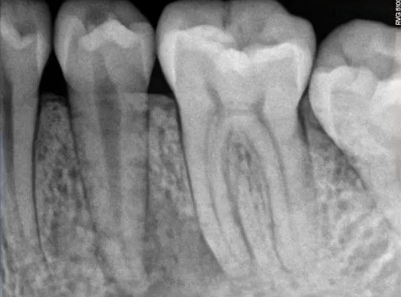

主要诊断:牙体——47龋坏伴根尖炎

牙列——35、45牙缺失,乳牙滞留,38、48智齿埋伏阻生

根尖片进一步诊断

47龋坏伴根尖炎

37继发龋!根尖炎?

25远中邻面浅龋